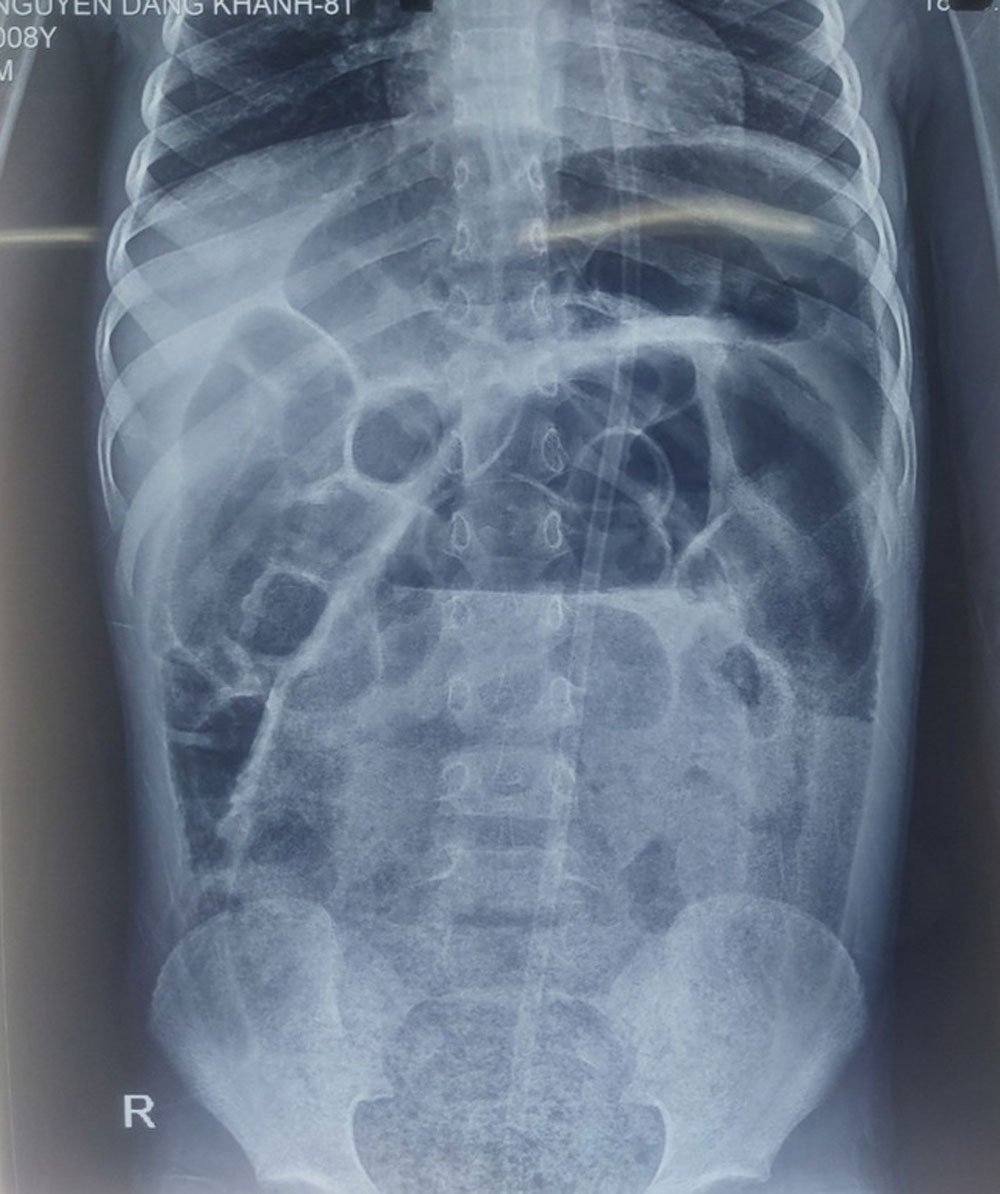

Tại khoa Phẫu thuật nhi, các bác sĩ thăm khám thấy trẻ bụng trướng căng, quai ruột nổi, bệnh nhi nôn dịch nâu bẩn, không đại tiện. Bóng trực tràng rộng, phía trên có khối phân to làm gấp đại tràng, dùng sonde không đẩy lên được để thụt tháo. Chụp X-quang quai ruột giãn to, chứa nhiều phân.

Hình ảnh X-quang các quai ruột giãn to và chứa nhiều phân ở cháu bé. |